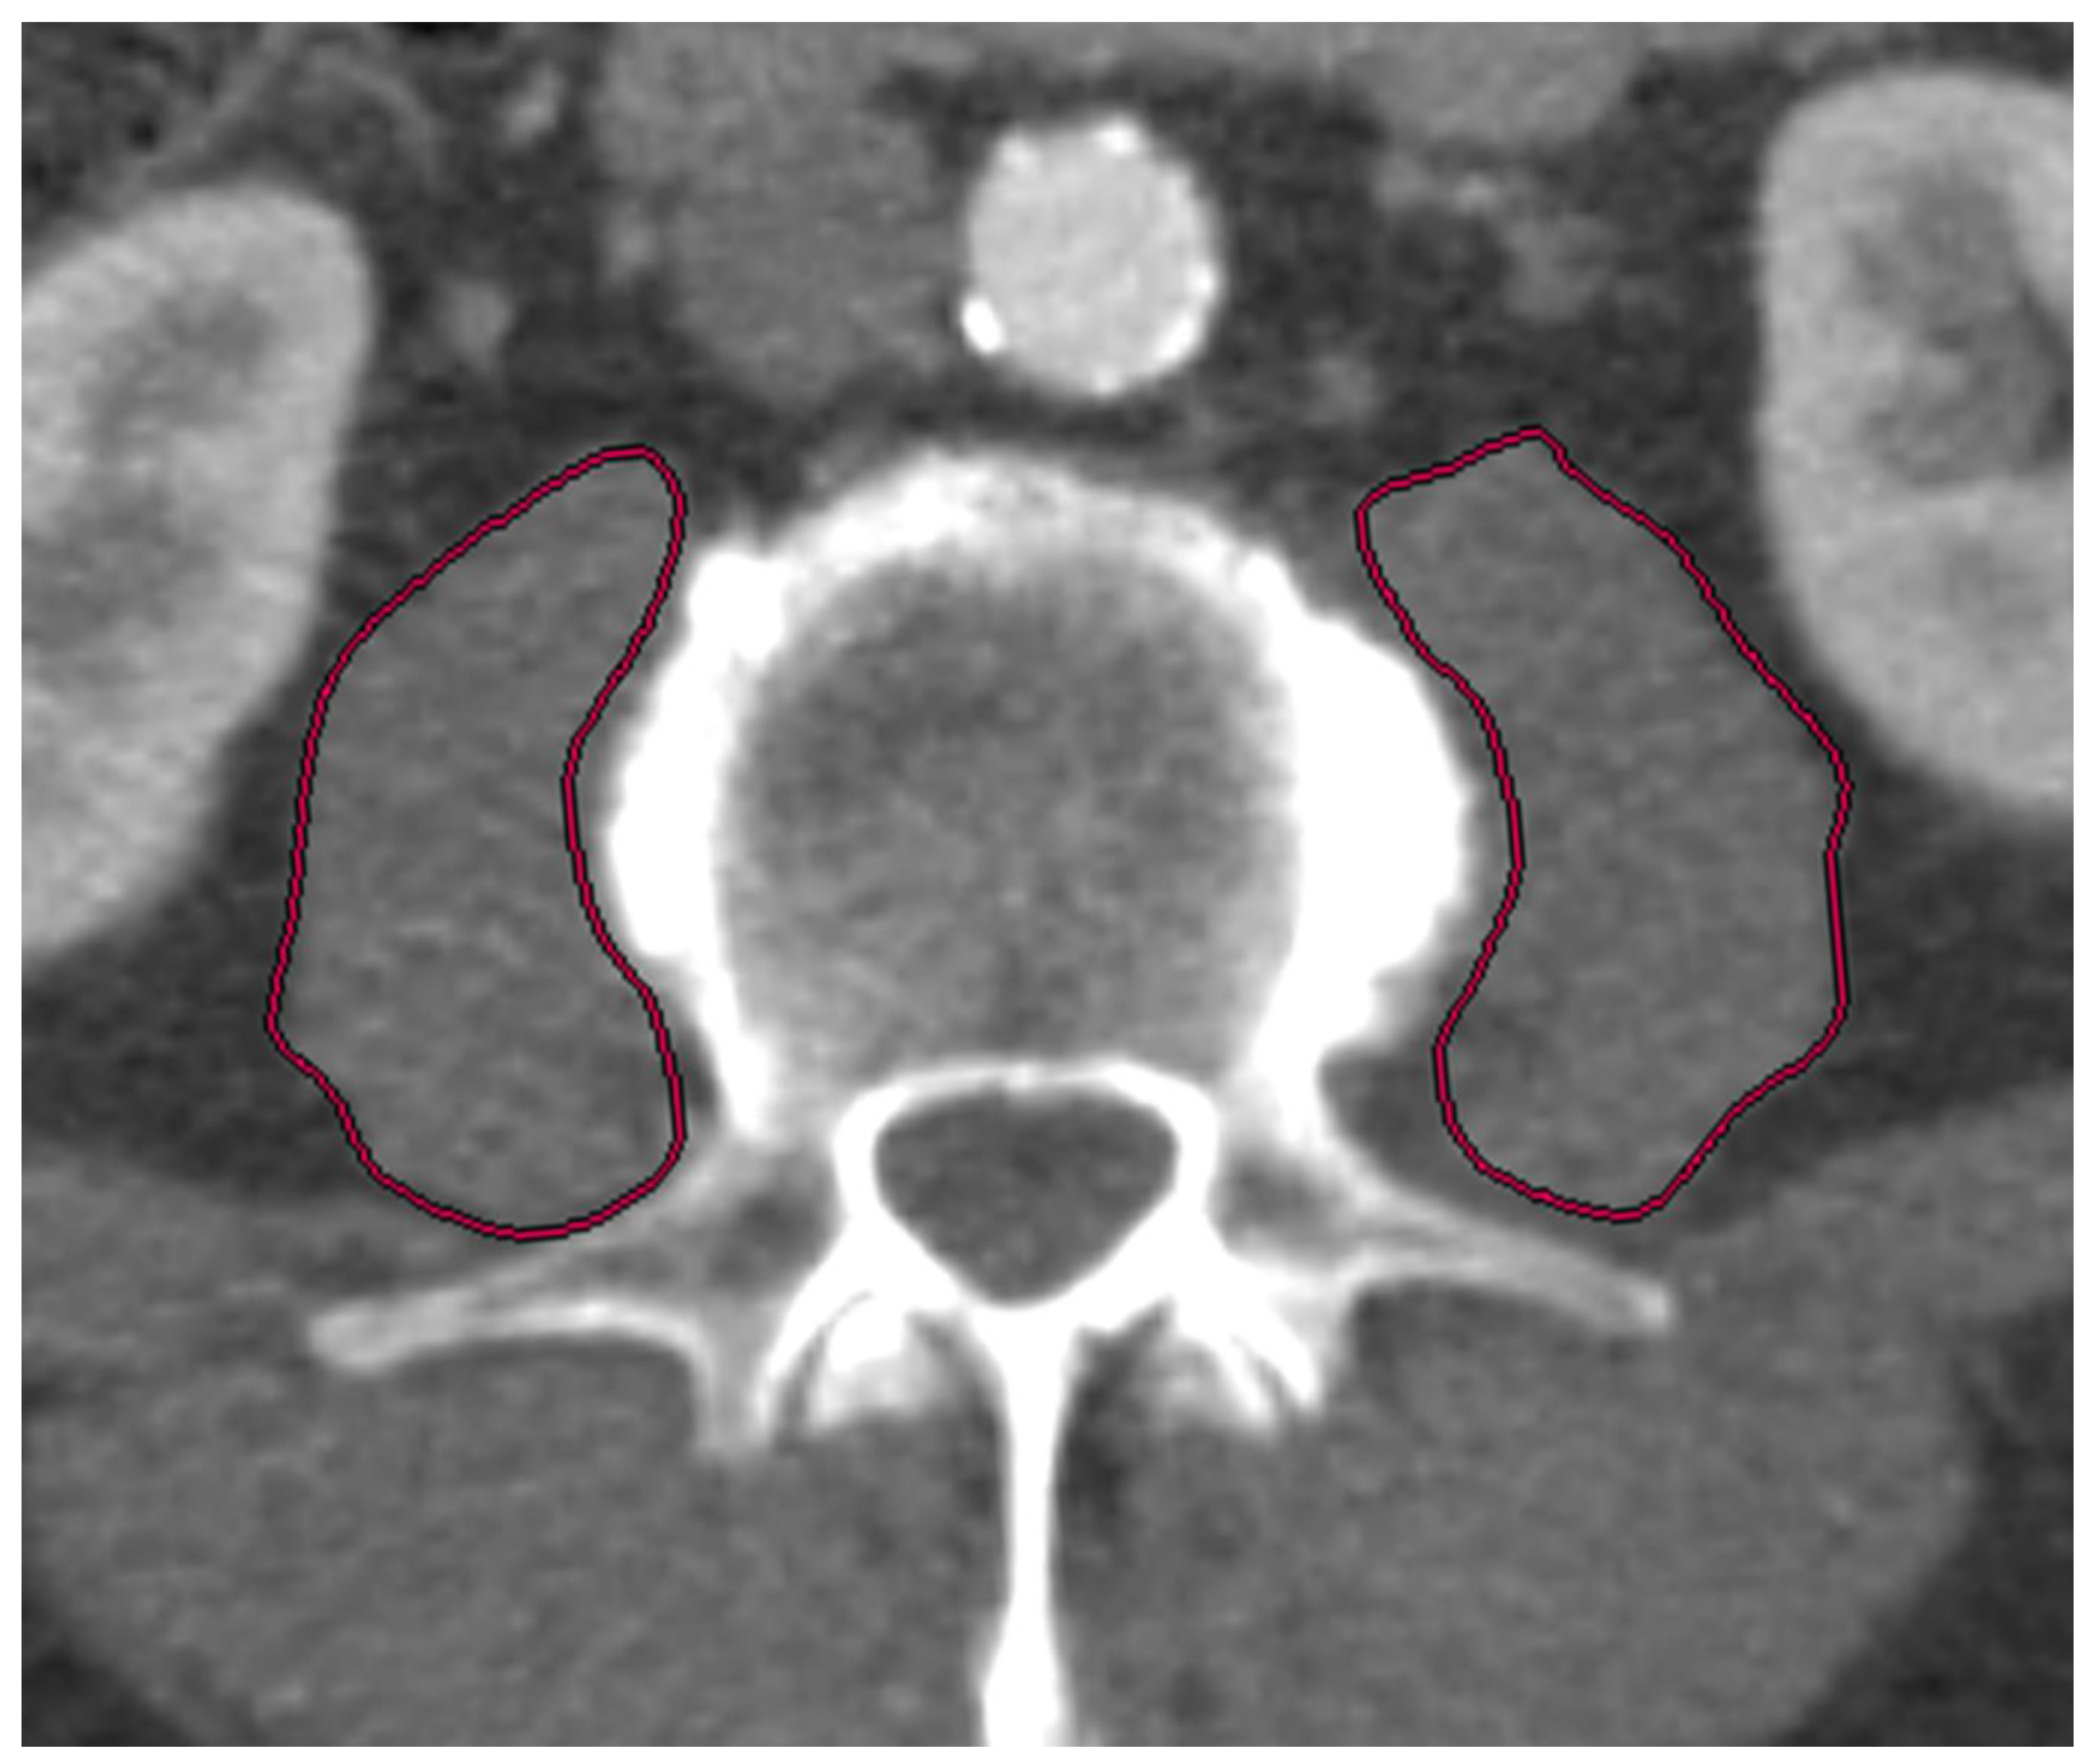

At both cardiological centers, patients received a pre-interventional, ECG triggered CT-angiography (CTA) of the entire aorta including the femoral arteries in order to assess, among others, aortic annulus size, aortic, coronary and general vascular anatomy and vascular access side for routine diagnostic workup. Two radiologists, one board certified with seven years of experience in vascular imaging (radiologist 1) and the other in the fourth year of training (radiologist 2), independently assessed the psoas muscle area (PMA: mm2). The radiologists were blinded to all clinical and laboratory data. Measurements were obtained on axial CTA scans of the entire aorta performed on a multidetector CT scanner with a patient size-adapted tube voltage (80–120 kVp) and active tube current modulation. A bolus-tracking technique was applied with a 100 mL bolus of non-ionic iodinated contrast media followed by 70 mL saline solution injected at a flow rate of 3.5–5 mL/s. Imaging data were analyzed using a soft tissue kernel with a slice thickness of 3 mm and a reconstruction interval of 2 mm. PMA was measured in all patients at the level of the superior endplate of the third lumbar vertebrae (L3) by manually outlining the right and left psoas muscles (Figure 1 and Figure 2). The total area of the psoas muscle was obtained by adding the areas of the left and right psoas muscles. Normalization to body surface area (BSA) yielded the indexed PMA (PMAi: mm2/m2). Measurements were performed on a picture archiving and communication system (PACS, Workstation, Impax; Agfa, Mortsel, Belgium).

Figure 1.

Process of slice selection using the Extended Multiplanar Reconstruction Plugin in IMPAX. The axial slice (a) was aligned parallel to the superior endplate of the third lumbar vertebrae at sagittal (b) and coronal (c) reconstructions.